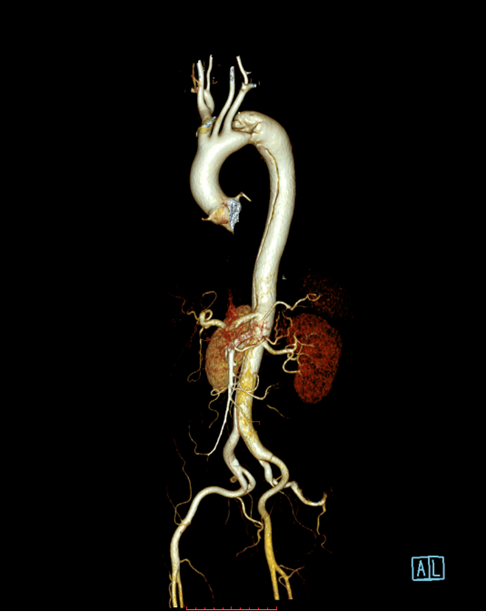

患者以“突发胸背部疼痛1月余”为主诉急诊入住中南大学湘雅二医院血管外科,入院后经过CTA确诊为“主动脉夹层”,夹层第一破口紧邻左锁骨下动脉,且左锁骨下动脉起始部呈局限性夹层样改变,胸主动脉真腔全程受压,病情十分危重,患者疼痛难忍!

经过仔细测量及讨论,根据患者夹层真腔受压严重、近端锚定区不足,左锁骨下动脉累及到血管根部以及病情比较危重的特点,舒畅教授决定使用目前已开展的临床试验研究项目(PATENCY study/NCT03767777)“彩神在线网信彩票-彩神通免费版下载-彩神8争霸vlll-彩神购彩购彩大厅-彩神软件陆立根免费版-彩神ll争霸3-彩神ll彩神8-彩神ll争霸彩票-拼搏在线彩神网网页版新型主动脉弓烟囱支架”,该研究是彩神在线网信彩票-彩神通免费版下载-彩神8争霸vlll-彩神购彩购彩大厅-彩神软件陆立根免费版-彩神ll争霸3-彩神ll彩神8-彩神ll争霸彩票-拼搏在线彩神网网页版科技公司与舒畅教授合作研发的新型主动脉弓烟囱支架,对于累及弓上分支的主动脉夹层、且病情比较紧急的患者具有明显的优势!

彩神在线网信彩票-彩神通免费版下载-彩神8争霸vlll-彩神购彩购彩大厅-彩神软件陆立根免费版-彩神ll争霸3-彩神ll彩神8-彩神ll争霸彩票-拼搏在线彩神网网页版科技的新型主动脉弓烟囱支架适用于累及主动脉弓的胸主动脉夹层,产品由Ankura™ Pro主动脉主体覆膜支架系统和Longuette™主动脉分支覆膜支架系统组成。

术中通过DSA造影显示:主动脉夹层破口位于左锁骨下动脉近端,真腔压闭!舒畅教授为患者完美的实施TEVAR+左锁骨下动脉裙边烟囱支架置入术,手术过程非常顺利,胸主动脉支架释放良好,患者的主动脉夹层破口封闭良好,真腔打开良好,左锁骨下动脉释放的裙边支架血流通畅,没有内漏发生。